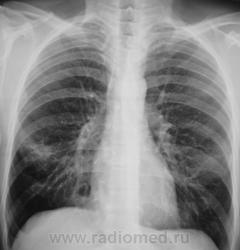

Контроль через 1 месяц после противовоспалительной терапии.